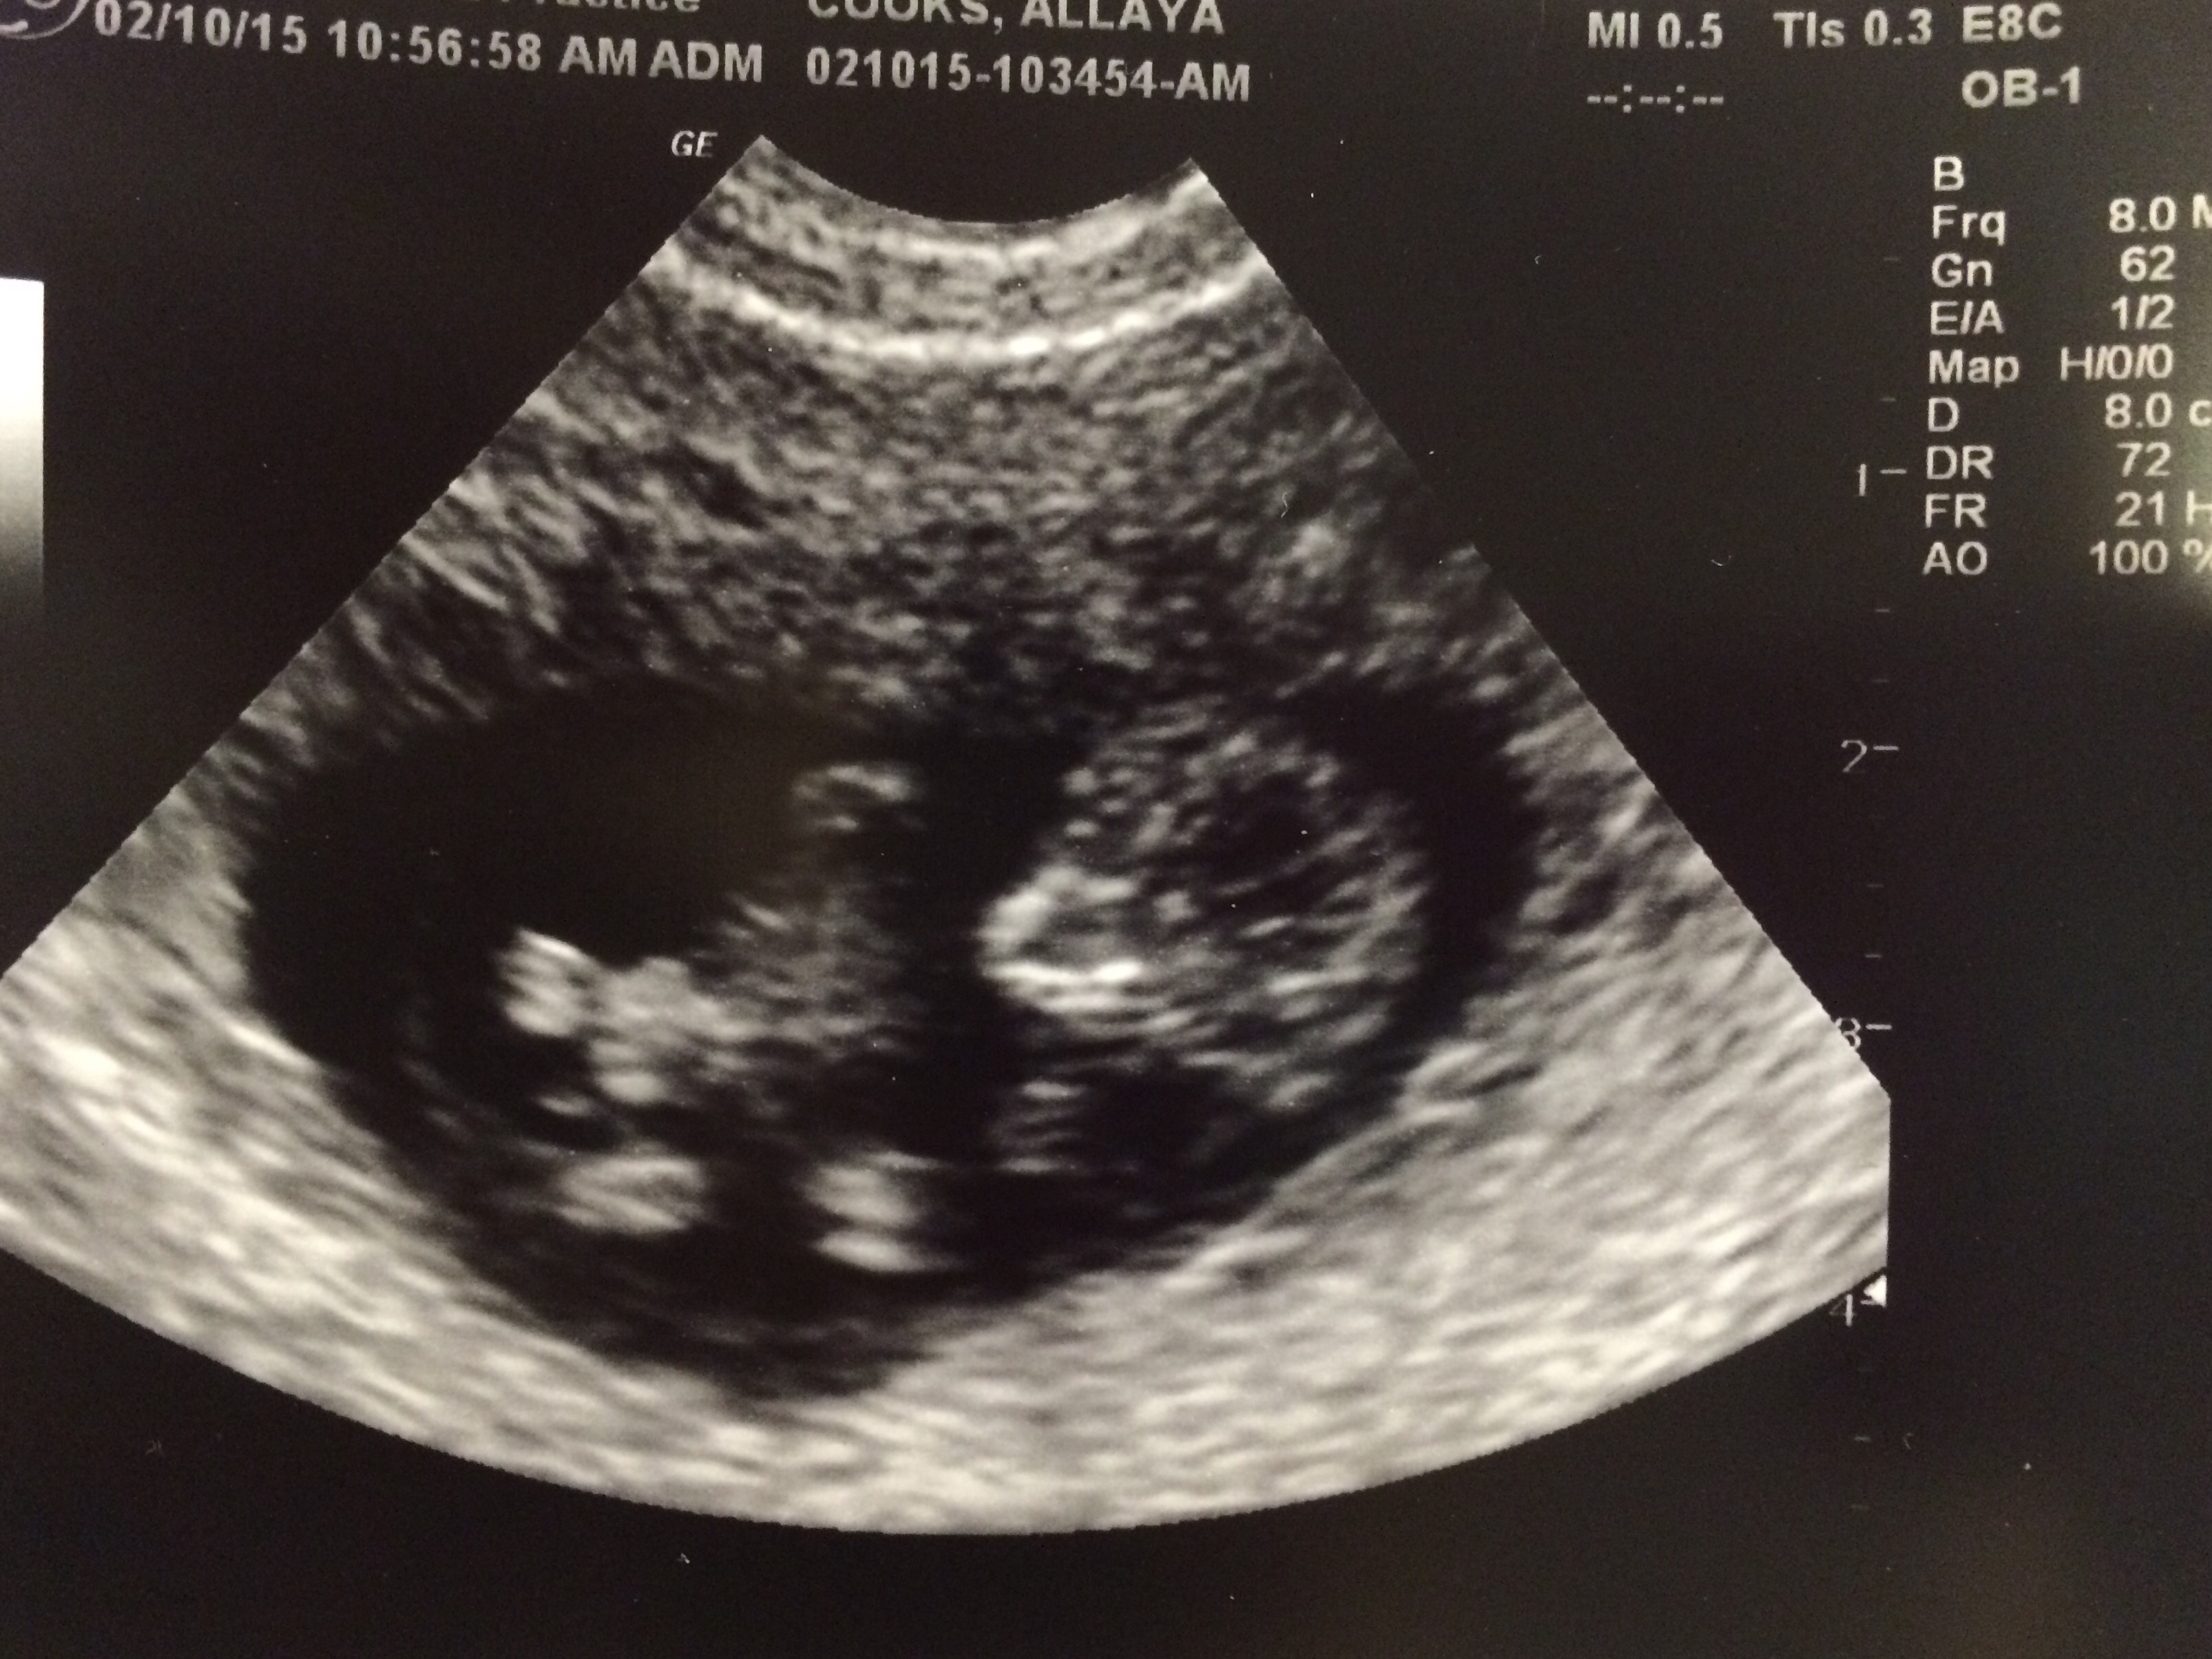

• Had my first US today and found out we're having twins! My husband and I are ecstatic, but terrified! Saw the babies heartbeats but don't know the rate.

• I had two u/s in the space of 5 days. The first was done at my first OBG visit along with blood work, it was basically to get an idea of how far along I was. Based on my LMP I would have been exactly 9 weeks but the u/s put me at 8 weeks 5 days, so it wasn't far off. My 2nd was done to ensure baby was ok due to bleeding and all is well thank goodness. But now I'm on restriction until the first trimester is complete. I'm a FTM so I'm still trying to wrap my mind around it, still don't think it's sunk in and I'm already 10weeks! Yikes!

I had 21 ultrasounds with my first pregnancy.  i'm  afraid that in my case, it is the combination of multiple risk factors and complications plus a little bit of bad luck, that causes the doctors to want to take a look early one and then frequently afterwards.  I had my second of two ultrasounds this week, bringing my total for this pregnancy so far up to 4 so far.  I have the next one scheduled already for march 2 as part of genetic screening testing.  i'm currently 9.5 weeks pregnant.